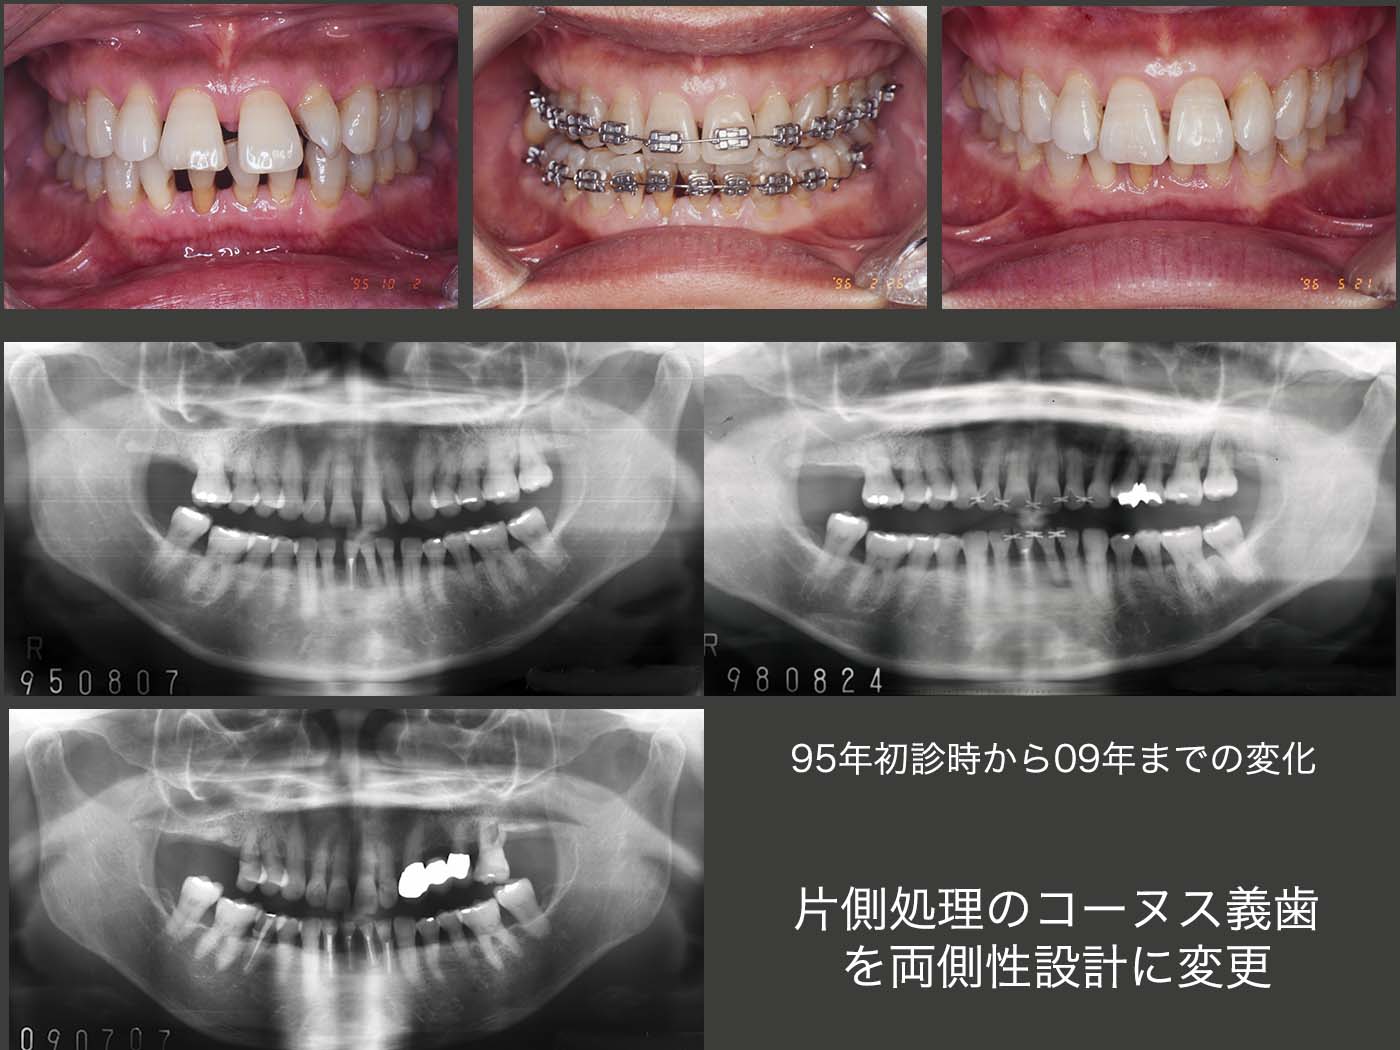

2.片側処理のコーヌス義歯を両側性設計に変更

1995年10月初診.49歳女性.主訴は歯周病の予防をしたい.歯周病の治療終了後に前歯の審美性向上を期待し,歯科矯正を行った.(スライド上段中央の写真は下顎前方位の状態)96年5月,治療は一段落ついた.その後定期的にリコールに応じてもらった.スライド中・下段に95年初診時から2009年までのパノラマX線写真を示す.歯のプラークコントロールは申し分ないが,咬合力が著しく強い.それが一番の原因と思われるが,咬合支持歯で主にここで食事をしていると思われる左上7を98年8月,左上4を00年6月,右上6を06年2月にそれぞれ歯周病で失った.なお,04年5月に右下5を歯冠破折から抜髄した.下顎2〜2の前歯は,咬合力によるアブフラクションおよび歯間ブラシの過度の使用から歯がすり減ったことが原因で抜髄した.

2011年9月,上顎大臼歯部唯一の残存歯であり,かつ咬合支持歯である左上6の歯周病が進行し,10月に抜去した.現状では臼歯部は小臼歯部での咬合となるが,小臼歯だけではこの患者さんの咬合力にはとても耐えることができないと判断した.そこで,コーヌス義歯を製作することにした.コーヌス義歯は義歯を介して歯をつなぐことができるので,歯の連結固定が得られ,咬合力に対抗できる利点がある.(2次固定)また,義歯床でも咬合力を担うことができる.さらに,仕事(美容師)中に,歯を接触(TCH)しないように常に意識すること,および食事中になるべく力を入れないように努力することをお願いした.

2012年9月,片側処理のコーヌス義歯を左右に装着した.いきなり両側性設計の義歯を装着すると違和感が生じやすいので,まずは口蓋を覆わない形にしたが,11月,装着して直ぐに右上4の歯周ポケットが悪化した.そこで直ぐに固定効果を増すために左右義歯床を連結する必要に迫られた.口蓋を覆う位置を実験的に検討したが,最終的に口蓋隆起を除去し,その空いたスペースに大連結装置を付与させてもらうということで了解してもらった.13年8月,パラタルプレートを装着し,両側性設計の義歯に改変した.

2018年12月までの5年4ヵ月間,特に問題なく経過した.しかし,19年7月,左上5の内冠が歯冠破折した.本来なら抜髄して,根管保持の補綴装置を製作するところであるが,今回は有髄のままOPAアタッチメントを装着した.(どこまで保てるか疑問ではあるが)なお,装着時に患者さんから左上3も外れていると言われたが,本当に左上3の内冠も歯冠破折していた.こちらはまだ歯肉縁上歯質が残っていたので,ピンを用いて内冠を再合着した.

2019年11月の状態.それにしても,有髄歯が2本続けて歯冠破折するとは想像していなかったとともに,有髄のままリカバリーできて本当に良かった.12年の時に心配した右上4は,両側性設計にすることで連結固定効果が強固になったことが幸いしたからか,その後小康を保っている.